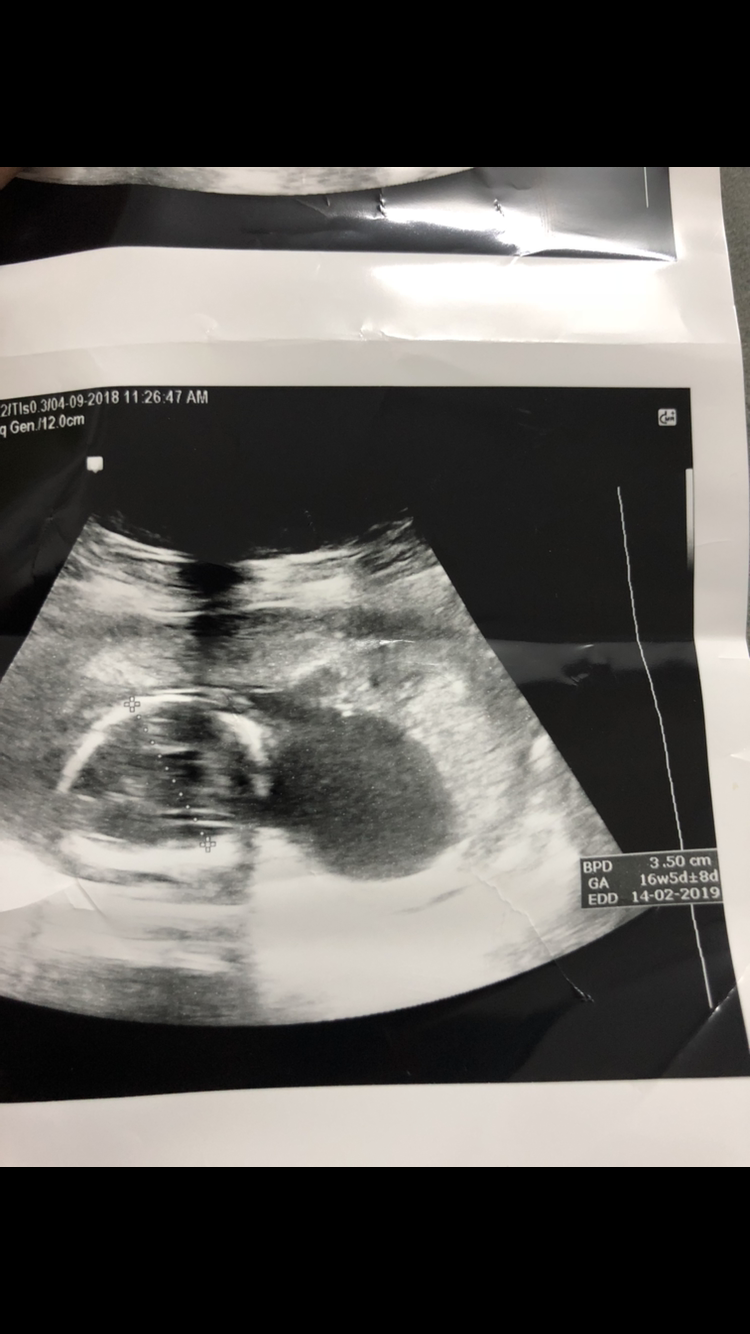

ولد اكيد كيس الصفن واضح بس العضو مو باين مره

سونارك اشوف عضووو

واضح

طيب الشاطره بسونار ايش اللي واضح بسوناري

نفس سوناري قالت لي بنت

طيب بنات وش في سوناري؟